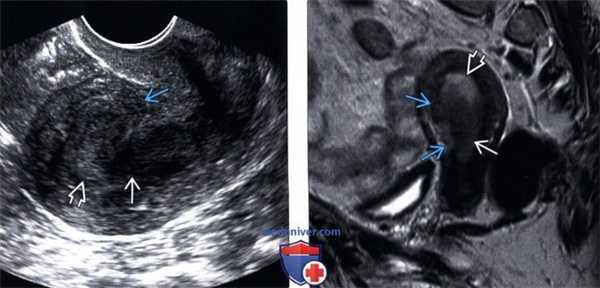

(Слева) Трансвагинальное УЗИ в продольной плоскости: определяется гетерогенное гипоэхогенное объемное образование, растягивающее полость матки. Передняя граница миометрия нечеткая, что указывает на инвазию. Визуализируется небольшое количество эхогенного эндометрия.

(Справа) МРТ, Т2-ВИ, сагиттальный срез: у этой же пациентки определяется гипоинтен-сивная опухоль, гиперинтенсивный эндометрий, и нарушение переднего участка переходной зоны, что указывает на прорастание миометрия. Результаты патологического исследования подтвердили наличие признаков эндометриоидного и папиллярного типов рака.